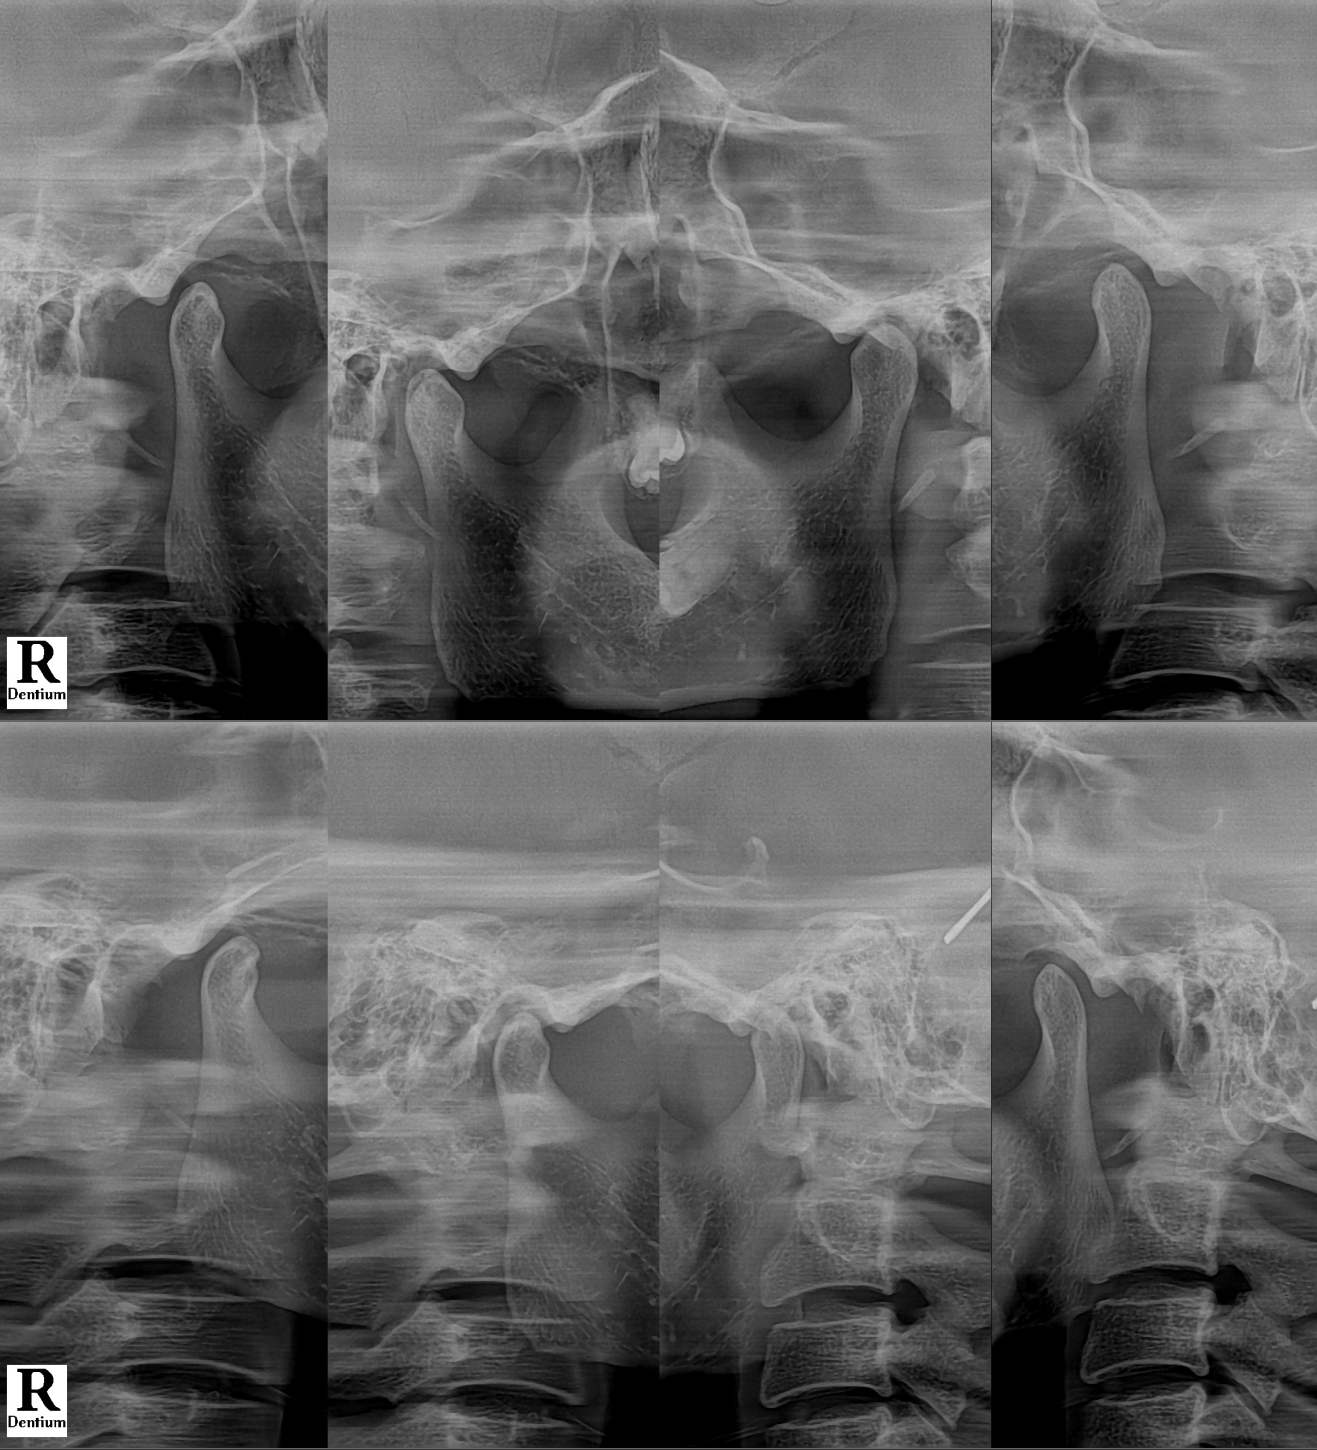

#CaseNo240475 턱이 어긋난 느낌이 있다면, 턱관절이 보내는 신호일 수 있습니다

이번 경우도

건강보험 진료로 총 5회 진행하면서

오른쪽으로 쏠린 상태를 줄이고

턱이 안정된 위치를 유지할 수 있도록 치료를 진행했습니다.